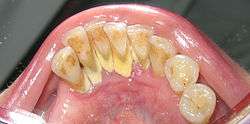

In dentistry, calculus or tartar is a form of hardened dental plaque. It is caused by precipitation of minerals from saliva and gingival crevicular fluid (GCF) in plaque on the teeth. This process of precipitation kills the bacterial cells within dental plaque, but the rough and hardened surface that is formed provides an ideal surface for further plaque formation. This leads to calculus buildup, which compromises the health of the gingiva (gums). Calculus can form both along the gumline, where it is referred to as supragingival ("above the gum"), and within the narrow sulcus that exists between the teeth and the gingiva, where it is referred to as subgingival ("below the gum").

The processes of calculus formation from dental plaque are not well understood. Supragingival calculus formation is most abundant on the buccal (cheek) surfaces of the maxillary molars and on the lingual (tongue) surfaces of the mandibular incisors.[13] These areas experience high salivary flow because of their proximity to the parotid and sublingual salivary glands. Subgingival calculus forms below the gumline and is typically darkened in color by the presence of black-pigmented bacteria,[13] whose cells are coated in a layer of iron obtained from heme during gingival bleeding.[14] Dental calculus typically forms in incremental layers[15] that are easily visible using both electron microscopy and light microscopy.[7] These layers form during periodic calcification events of the dental plaque,[13] but the timing and triggers of these events are poorly understood. The formation of calculus varies widely among individuals and at different locations within the mouth. Many variables have been identified that influence the formation of dental calculus, including age, gender, ethnic background, diet, location in the oral cavity, oral hygiene, bacterial plaque composition, host genetics, access to professional dental care, physical disabilities, systemic diseases, tobacco use, and drugs and medications.[13]